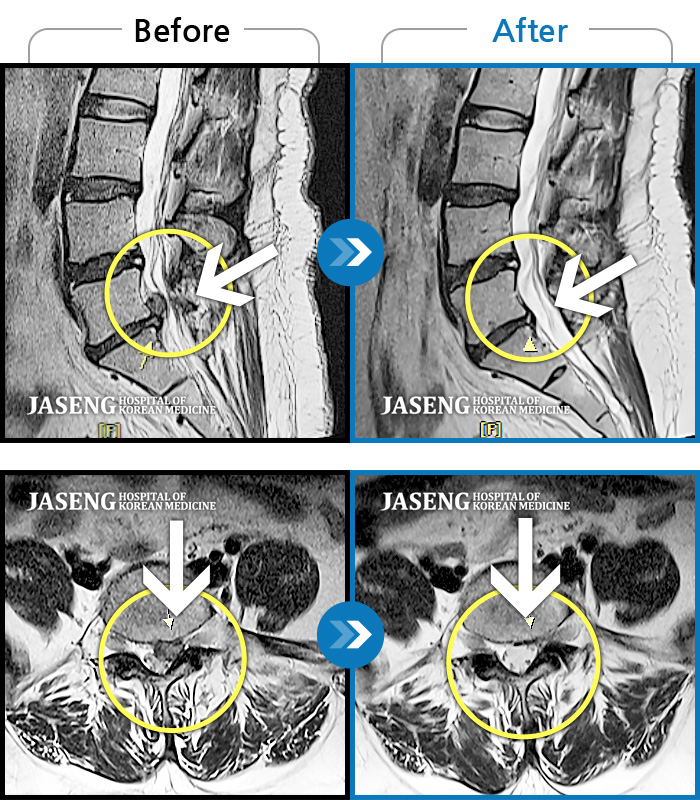

Before

After

허리 통증과 우측 허벅지 통증 및 저림 증상 지속되어 내원하셨습니다.

2022.08.20 ~ 2024.11.08